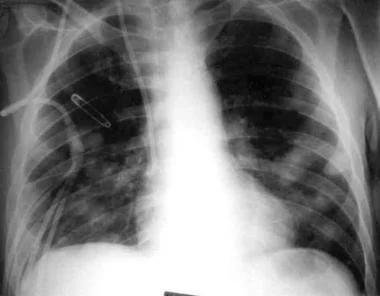

影像学检查是诊断真菌性肺炎的重要手段。胸部X线和CT扫描可以显示肺部的炎症情况,但其表现往往缺乏特异性。根据梅斯医学的报道,真菌性肺炎的影像学特征包括肺结节、晕征、反晕征等。然而,这些特征并非真菌性肺炎所特有,还需要结合其他检查方法进行综合判断。